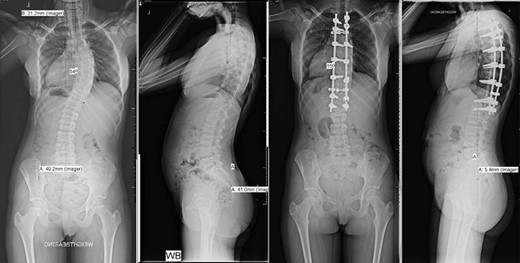

Pre- and post-operative spinal X-rays demonstrating 54° scoliosis curve, corrected with posterior fusion from T3 to L1.

A 15-year-old female with SCD underwent posterior scoliosis correction. One year prior to the surgery, she presented with two-year post-menarchal adolescent idiopathic scoliosis with right-sided trunk shift and rib hump, which was not fully reduced using the Adam’s forward bend test with right-side bending. There were no neurological signs or symptoms and no pain or functional impairment. X-ray showed that she was Risser stage 0 and had a right-sided mid-thoracic 40° curve from T4 to T11, which was maximal at T7, which progressed to 50° over 6 months. MRI showed biconcave ‘codfish’ vertebral deformities.

She underwent a posterior spinal fusion from T3 to L1 utilizing all pedicle screw construction. Total intravenous anaesthetic was employed to allow use of intraoperative trans-cranial spinal cord monitoring. A Misonix ultrasonic bone cutter was used for the facetectomies, and two diathermy generators were available for bipolar and monopolar use. Only one suction instrument was used and no cell saver. Generous Haemostat Surgiflo was used in each pedicle following instrumentation, and Spongostan foam, Surgicel and bone wax at the osteotomy sites. To further reduce bleeding, the mean arterial pressure (MAP) was maintained <70 mmHg and a costoplasty was avoided despite the rib hump. The total operation time was 220 min with 300 mL estimated blood loss (Fig. 1).